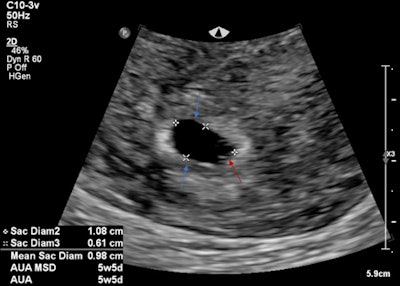

Intrauterine gestational sac with fetal pole. All images courtesy of Dr. Jeffrey Alexis and Dr. Patricia Deonarine, presented at RANZCR ASM 2022.

A 19-year-old female presented with suprapubic pain and a positive beta HCG. The initial ultrasound findings demonstrated both an intrauterine pregnancy and nonspecific adnexal mass. The intrauterine gestational sac featured both a gestational and yolk sac but no fetal pole. This correlated to an estimated gestational age of 5 weeks and 5 days. A heterogeneous left adnexal structure was demonstrated without internal vascularity. The left ovary was not readily identified. A hemoperitoneum was also present. The differential for the adnexal mass was thought to include a ruptured hemorrhagic cyst along with ovarian torsion and heterotopic pregnancy (see figures below).

Intrauterine gestational sac (blue arrows) and yolk sac (red arrow). No fetal pole identified.